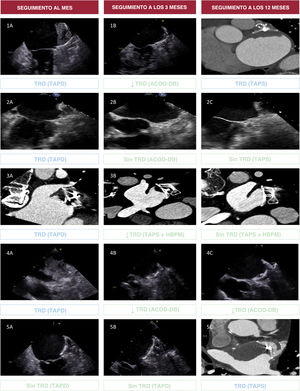

MétodosEl ensayo ADALA fue un ensayo clínico aleatorizado y multicéntrico en el que participaron 91 pacientes con fibrilación auricular y contraindicaciones para la anticoagulación oral. Tras un COI llevado a cabo con éxito, se aleatorizó a los pacientes a recibir tratamiento con dosis bajas de ACOD o TAPD durante 3 meses, seguido de TAPS. El objetivo principal fue una combinación de episodios tromboembólicos, formación de un trombo relacionado con el dispositivo (TRD) o hemorragias mayores tras 1 año de seguimiento.

ResultadosA los 12 meses, el objetivo principal fue significativamente menor en el grupo con dosis bajas de ACOD en comparación con el grupo de TAPD (el 9,1 frente al 32,6%; HR=0,25; IC95%, 0,08-0,74; p=0,013), principalmente debido a la menor incidencia de TRD (el 0 frente al 11,6%; p=0,023). El número de episodios de hemorragia mayor fue inferior con dosis bajas de ACOD (el 9,1 frente al 19,6%; p=0,167), y la tasa de hemorragias se redujo de forma significativa (el 13,6 frente al 37,0%; p=0,013). En el análisis de referencia se observaron diferencias significativas durante los primeros 3 meses (p <0,001), pero no desde los 3 a los 12 meses (p=0,195). Todos los casos de TRD tratados con dosis bajas de ACOD (n=4) se resolvieron por completo sin presentar hemorragia.

ConclusionesEn comparación con el TAPD, la administración de dosis bajas de ACOD redujo la aparición de episodios tromboembólicos y hemorrágicos durante el primer año tras el COI, como consecuencia de la menor incidencia de TRD temprano. La ausencia de TRD tras la suspensión del tratamiento con dosis bajas de ACOD respalda su uso durante 3 meses, seguido de TAPD, en esta población de alto riesgo.